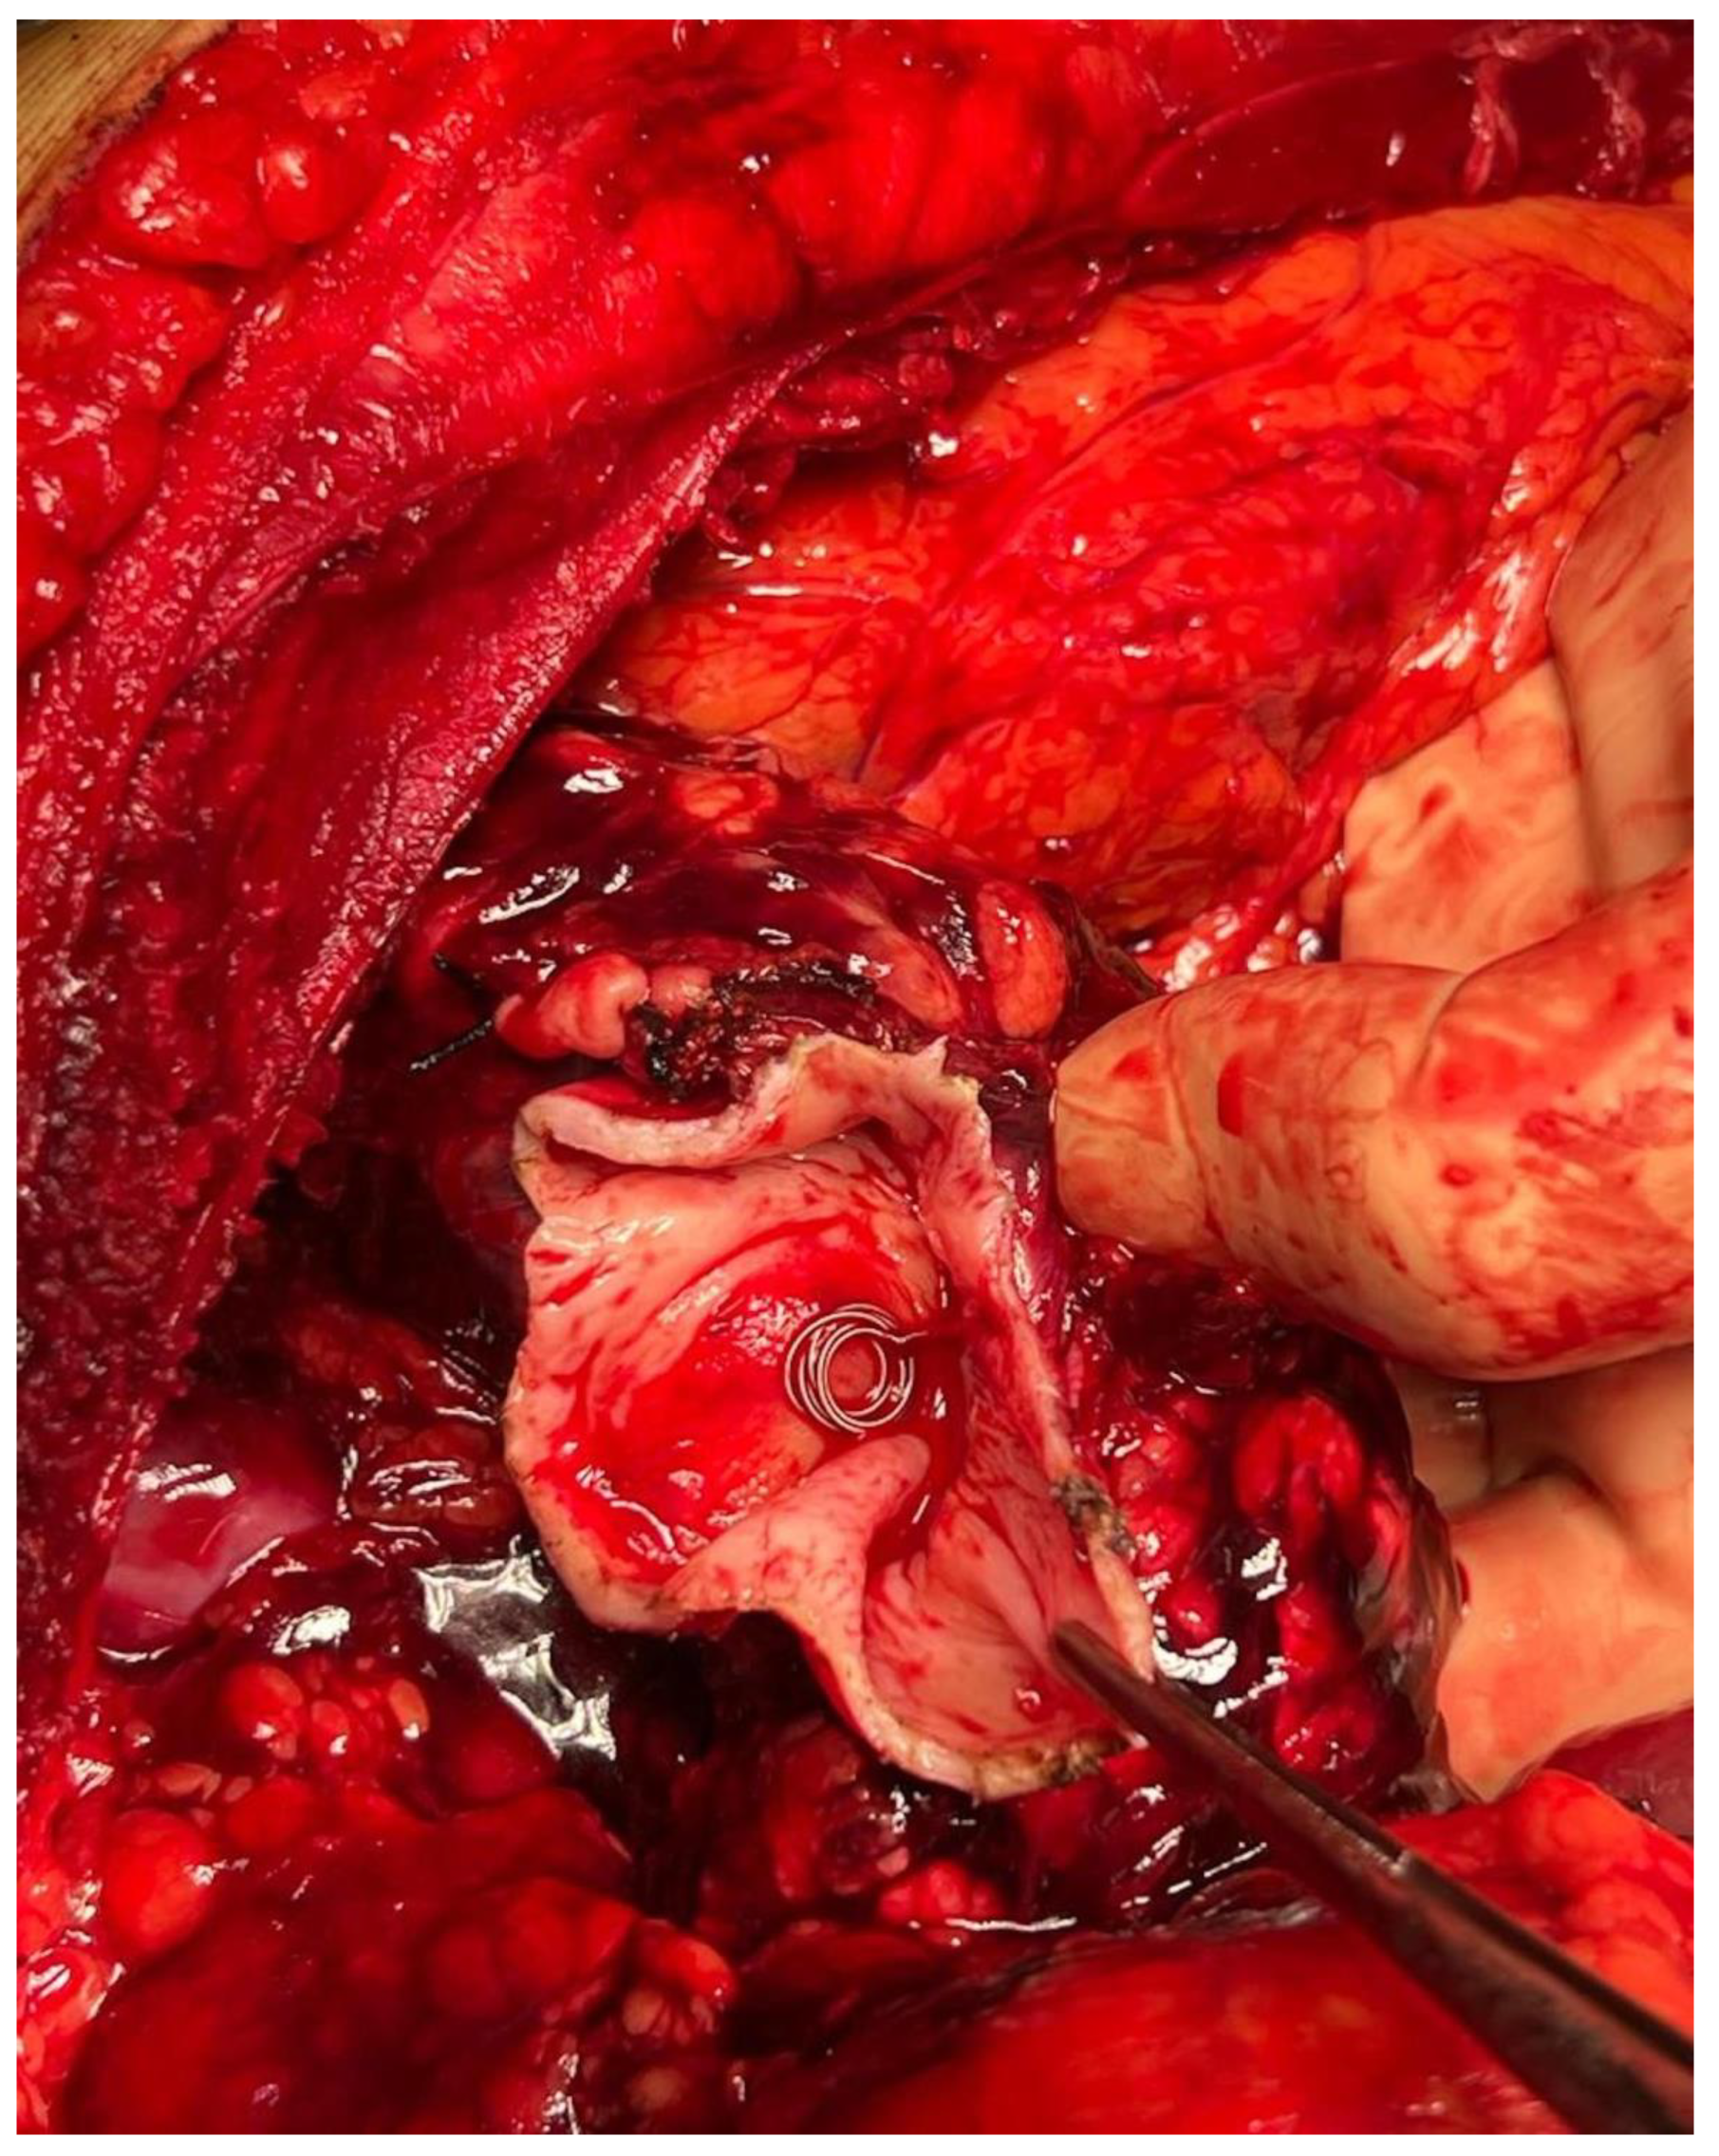

2.1. Case Report